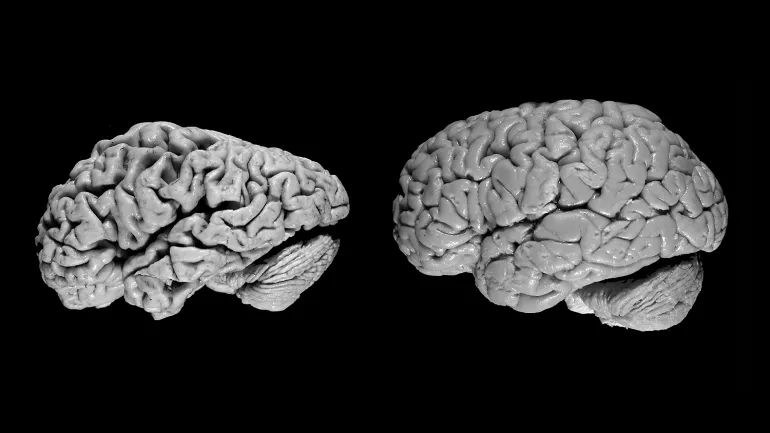

对阿尔茨海默氏症患者大脑的PET扫描

阿尔茨海默症患者的大脑(左)与未患此病的患者的大脑进行比较。